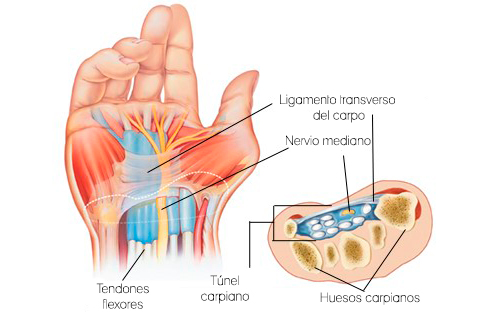

Síndrome del túnel carpiano (CTS)

Es uno de los problemas más comunes que afectan a la mano y la muñeca. Se produce cuando el nervio mediano, que se extiende desde el antebrazo hasta la mano, está presionado o apretado. El nervio mediano proporciona sensación y movimiento al lado de la mano en el que se encuentra el dedo pulgar. Esto incluye la palma de la mano, el dedo pulgar, el dedo índice, el dedo corazón y el lado del dedo anular del lado del pulgar (no dedo meñique).

El túnel carpiano es una estrecha y rígida vía de paso del ligamento y los huesos en la base de la mano. El engrosamiento de los tendones irritados u otras inflamaciones estrechan el túnel y hace que el nervio mediano quede comprimido. El resultado puede ser el dolor, debilidad o entumecimiento en la mano y la muñeca, que irradia hasta el brazo. La cantidad exacta y el tipo de movimientos repetitivos realizados durante trabajos dentales aún no ha sido cuantificada por estudios anteriores. Sin embargo, algunos investigadores han puesto de manifiesto que uno de los factores predictivos de la alta prevalencia de CTS entre los higienistas dentales es en períodos de clínica largos cuando se realizan movimientos repetitivos.